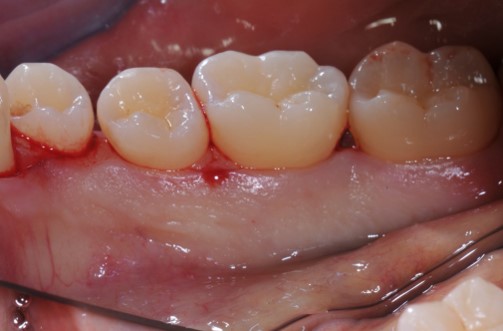

Contained intrabony defect treated using Straumann® Emdogain® - Kasaj

Radiographic view before periodontal regenerative therapy with Straumann® Emdogain®. A deep intrabony defect appeared mesially and distally on the left mandibular first premolar. Pre-surgical probing measured 8 mm. The defect morphology presented as well-contained.